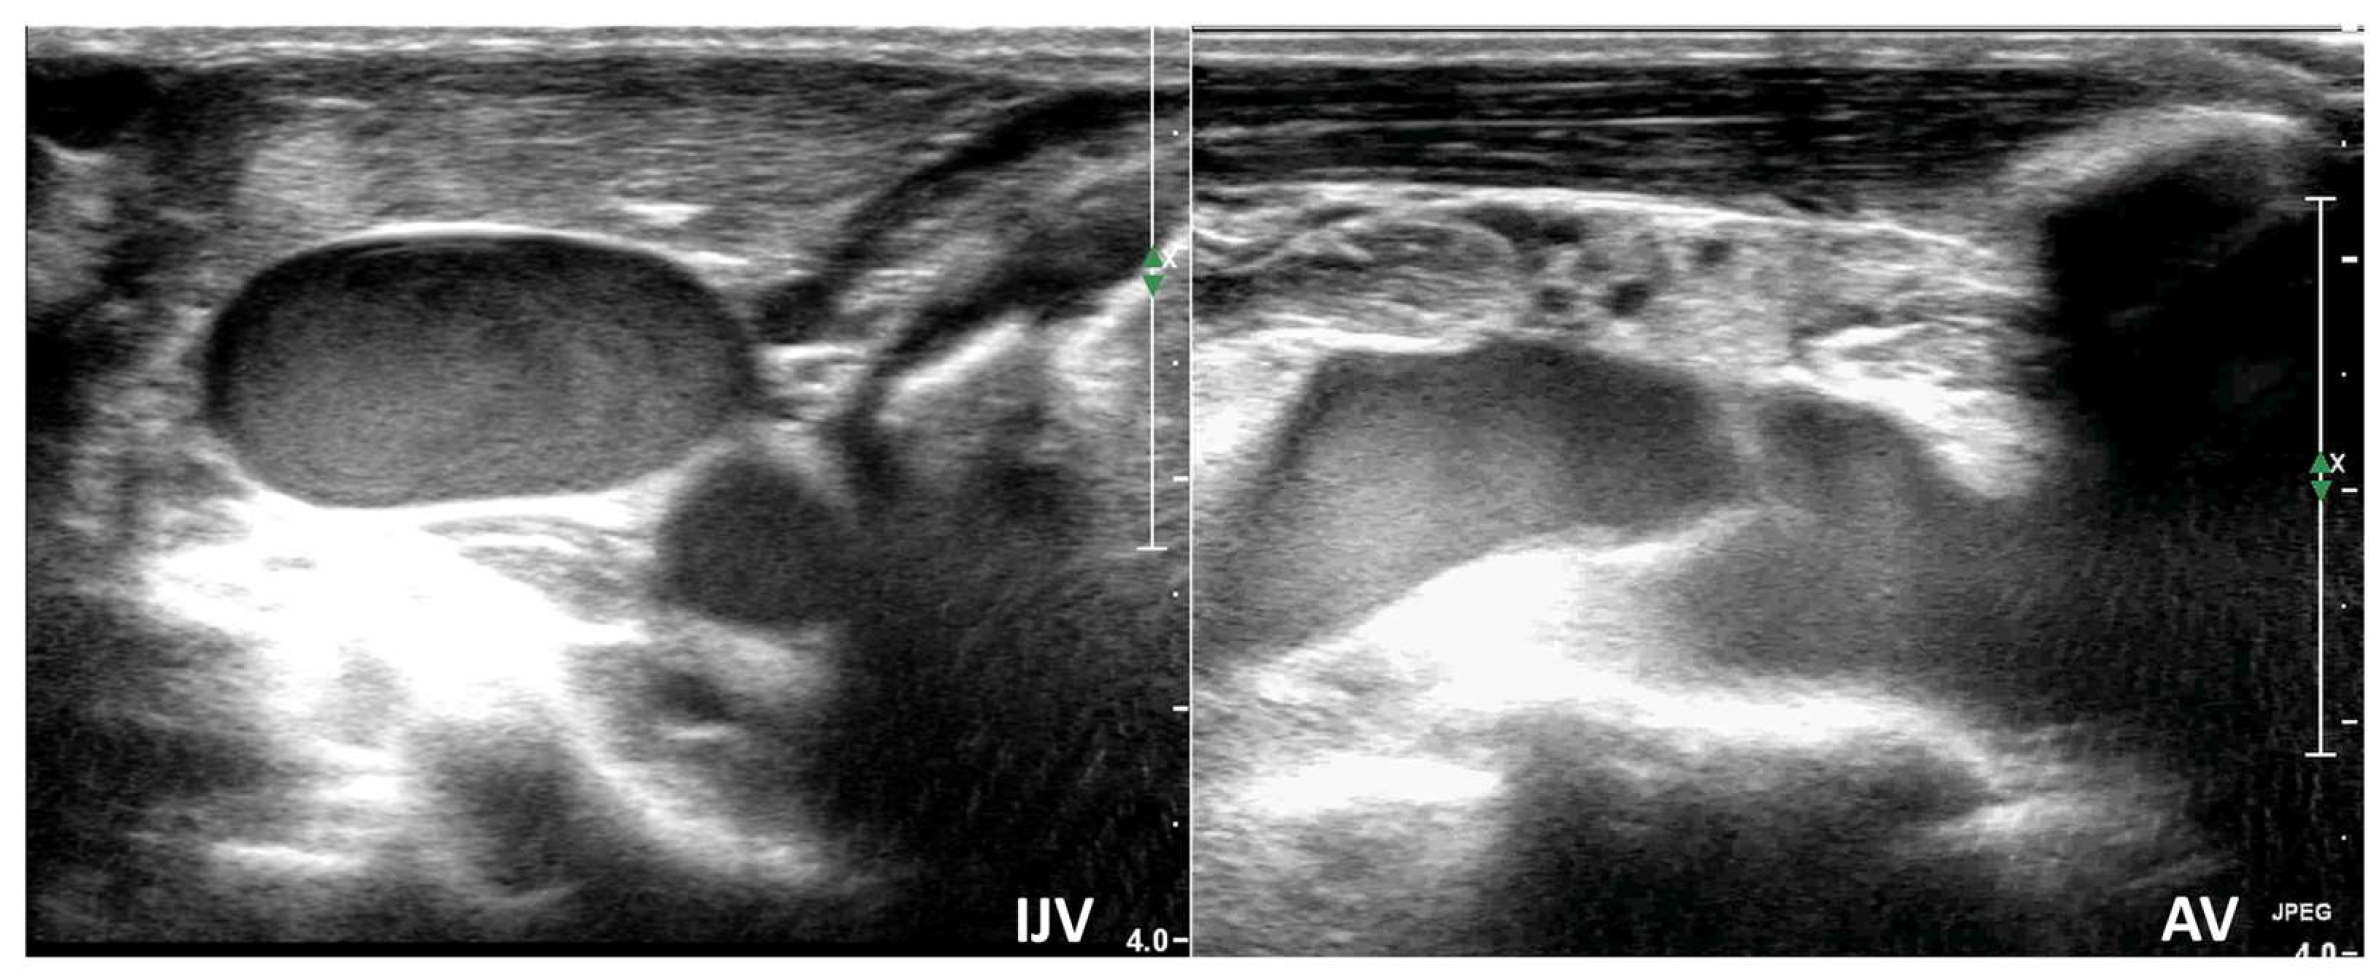

3.1.5. Centrally Inserted Central Catheters (CICC)

- Venous TCCD, combined with IJV ultrasound, offers real-time, early detection of cerebral venous outflow impairment, allowing timely and targeted adjustments to prevent secondary IH in critically ill and surgical patients.